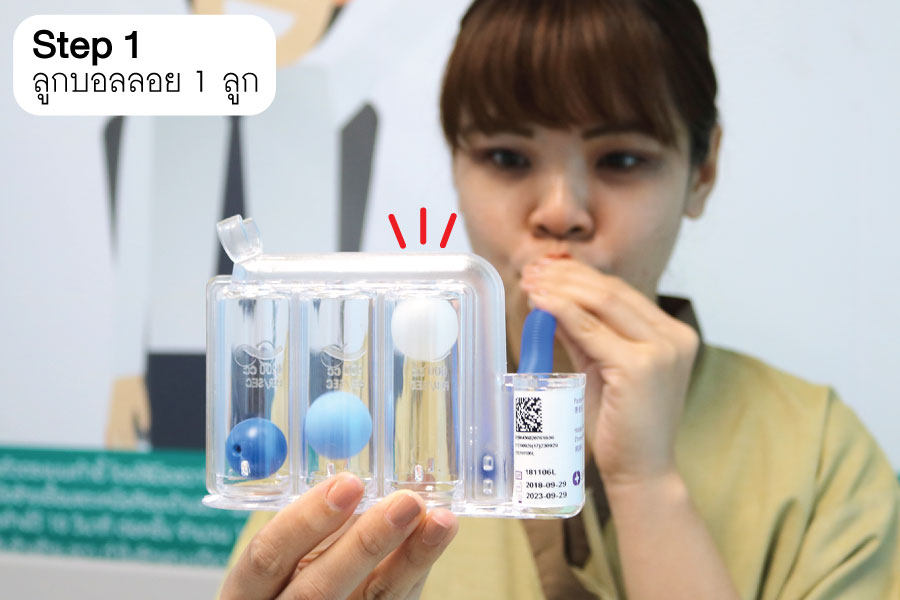

วิธีการใช้งาน Incentive Spirometer

- 1. ผู้ป่วยลุกนั่งหรือไขหัวเตียงให้สูงขึ้นถือ Triflow ตั้งขึ้นอมปากคาบไว้ในปาก ปิดริมฝีปากให้สนิท

- 2. หายใจเข้าออกปกติ เพื่อให้คุ้นเคยกับเครื่องก่อน จากนั้นให้ดูดช้าๆ และลึกๆ หายใจค้างไว้นานเท่าที่จะทำได้ (อย่างน้อย 5 วินาที) แล้วจึงปล่อยลมหายใจออก พักประมาณ 2 - 3 วินาทีแล้วจึงเริ่มต้นใหม่